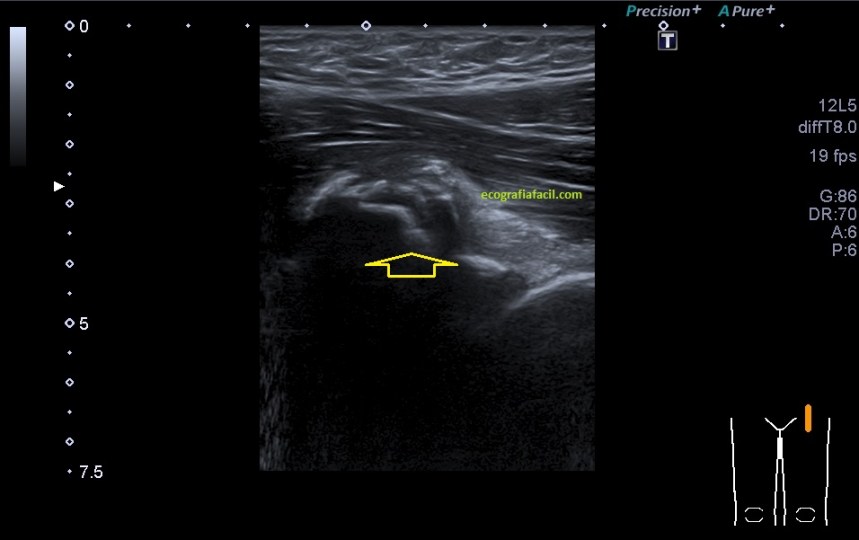

Lo único que me me llamó la atención fue la ecogenicidad (fig 1) de uno de los músculos del cuádriceps, en concreto el Recto Anterior, músculo anterior de la línea media de la musculatura en la cara anterior. Esta ecogenicidad era discretamente más ecogénica de lo habitual, sabemos que los músculos son hipoecogénicos por definición.

Inmediatamente exploré la misma zona del muslo contralateral, comprobando efectivamente los cambios en la ecogenicidad del músculo y cambios en el grosor, claramente disminuido en el lado afecto.

Un breve recuerdo anatómico de la zona tanto en eje largo como en eje corto (longitudinal o transverso), fig 3 y 2 respectivamente, . Fíjese la/el lectora en el posicionamiento del pictograma de referencia.